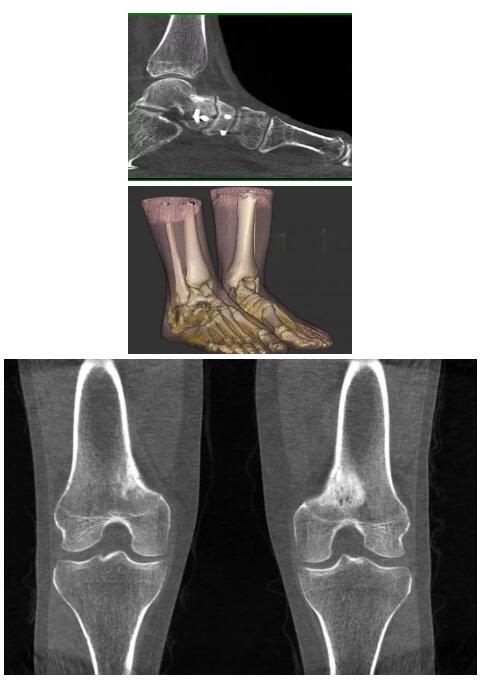

另外一款被稱為世界上最小的CT,它的重量僅300磅,不僅能夠掃查足部,還可以檢查膝蓋和上肢等。

與上面介紹的CT一樣,它同樣具有輻射低、占地空間?。?3*36)的特點,隨開隨用(支持直接接入墻上的插座)。

這款CT使用非常方便,通過上下移動保持與患者的手臂或者雙腿齊平,掃描快速,僅需要30秒左右就可以完成掃查。

以下是這些“特立獨行”的CT所拍出來的圖像: